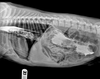

For the past 8 years, Veterinary Practice News has had an annual x-ray contest for the craziest things pet's have eaten. Here are the winners for 2013.